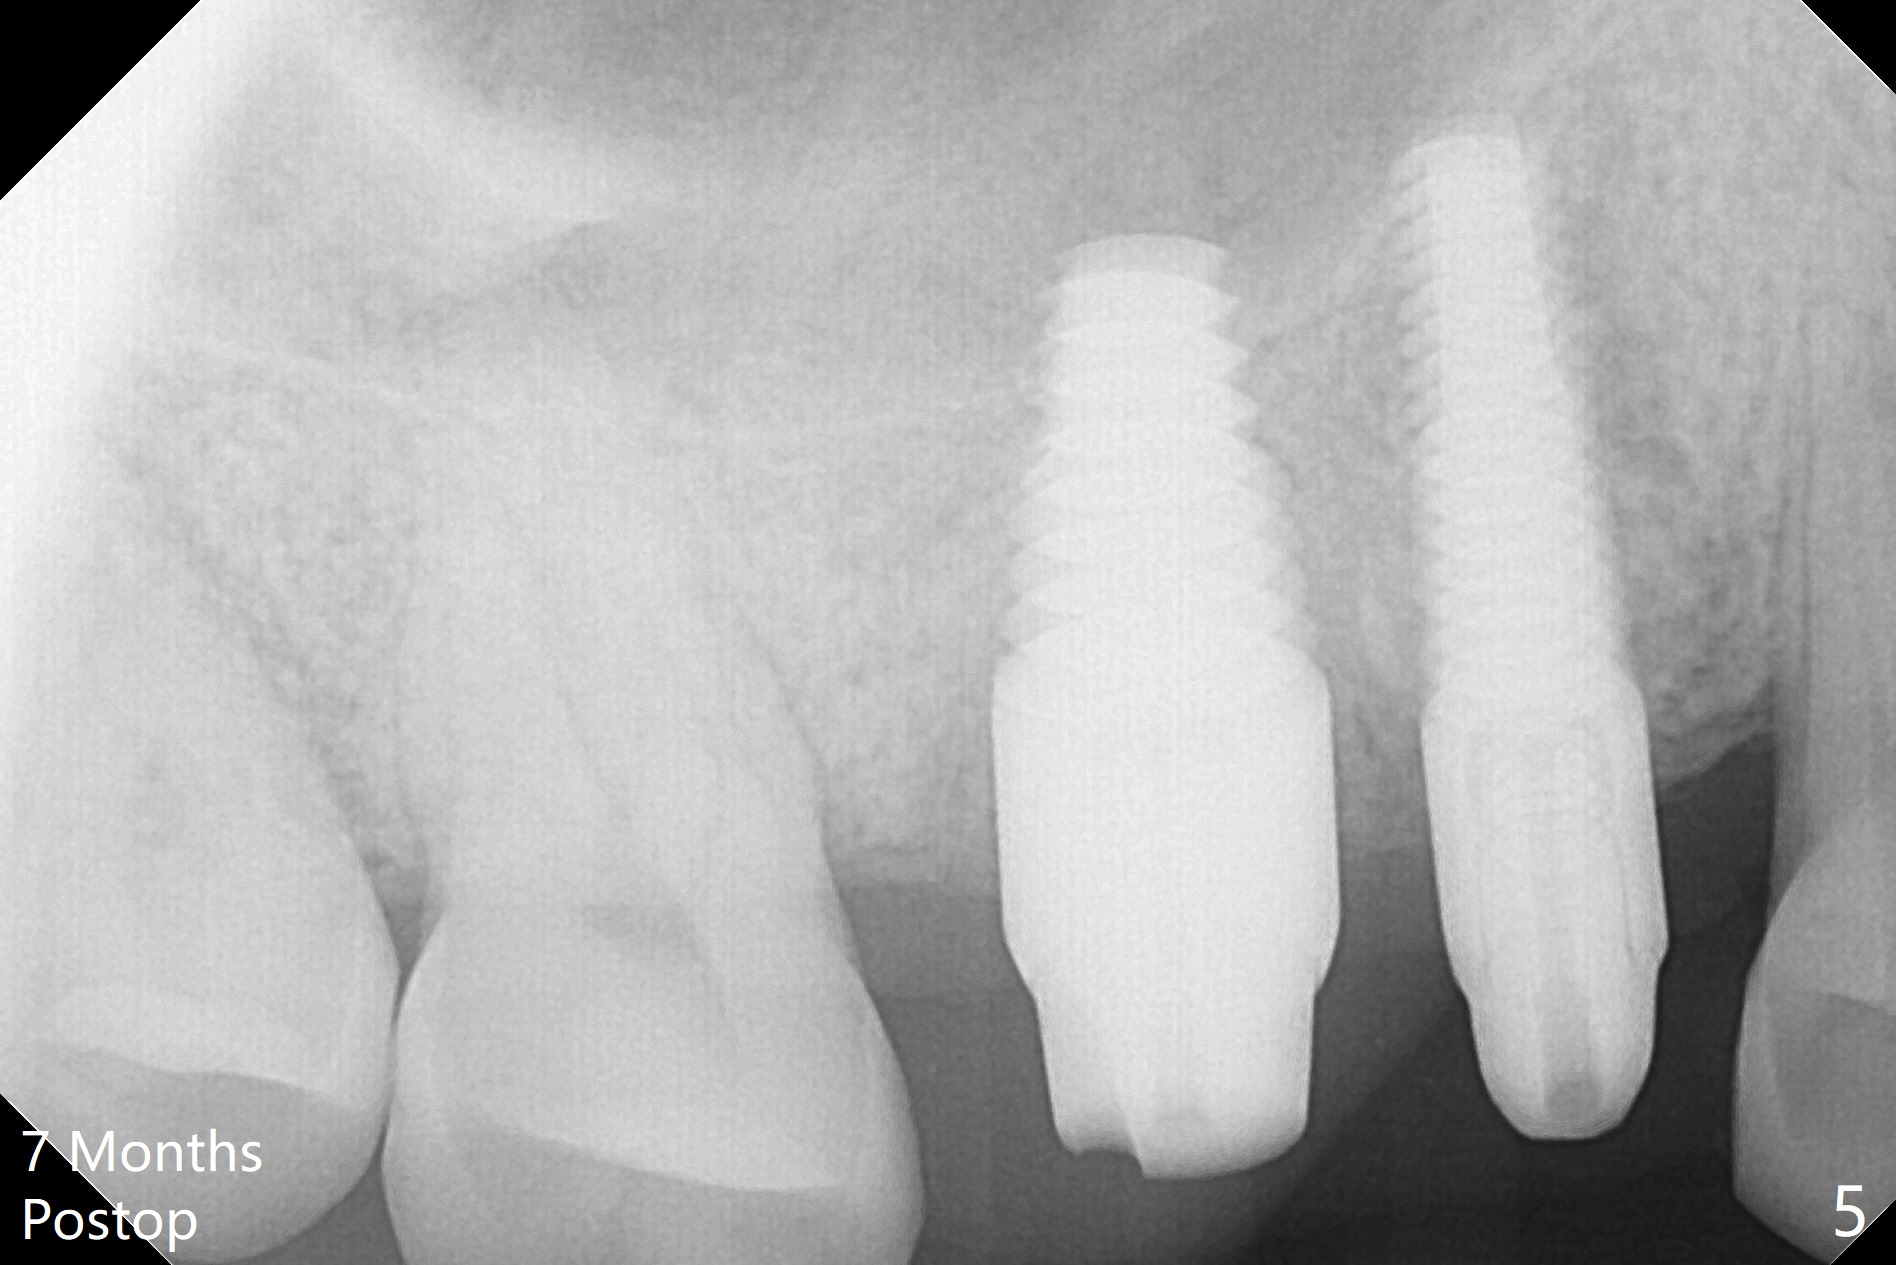

With proper manipulation, a 6x14 mm implant is placed with primary stability (Fig.3). The buccal and palatal socket opening is closed with Vera Graft (allograft, Fig.4 *), which is in turn covered by an immediate splinted provisional. No gap exists 7 months postop (Fig.5,6). Return to Upper Molar Immediate Implant, Prevent Molar Periimplantitis (Protocols, Table), IBS Xin Wei, DDS, PhD, MS 1st edition 09/26/2017, last revision 04/24/2018